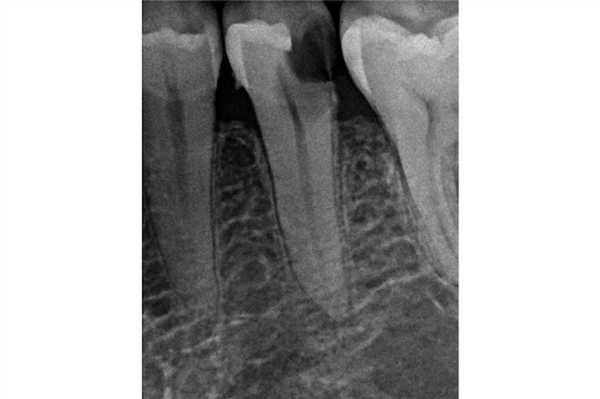

Фото 5. Лечение корневого канала, стекловолоконный штифт и композитный основной материал UL4. Циркониевую коронку установил общий стоматолог (Dr Davesh Patel) с использованием DME.

2. Нарушение биологической ширины

Фото 6. Кариозное поражение зуба UR6 было достаточно обширным и распространялось на поддесневую область. Врачу удалось добиться восстановления глубокого края дефекта, однако при этом произошло нарушение первичных параметров биологической ширины.

Почему DME важно для эндодонтии?

В эндодонтии врачи часто встречаются с зубами, один из краев дефекта которых находиться глубоко под деснами. По сути, DME дает шанс зубу «выжить», ведь без подобного подхода такой зуб можно категоризировать как такой, что не подлежит восстановлению (фото 7). Эффективное восстановление глубокого края дефекта часто является наиболее сложной частью лечения и занимает больше всего клинического времени.

Фото 7. Пациент обратился за стоматологической помощь по поводу кариеса корня и возможности восстановления зуба LR6. В ходе первого визита был очищен весь кариес и удалена старая пломба, после чего приступили к DME. Эндодонтическое лечение проводили в ходе второго визита. В дистальный канал установили стекловолоконный штифт, а всю дистальную поверхность восстанавливали посредством композита. Пациент был направлен к лечащему врачу для изготовления непрямой реставрации.